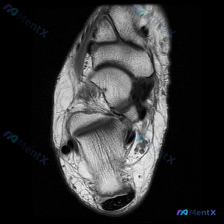

踝关节MRI看到大范围软组织水肿,这个病例的鉴别思路分享

这是一例踝关节矢状位T2加权MRI,我把影像发现和分析思路整理出来,和大家一起讨论。

这是踝关节MRI T2序列矢状位图像,可观察到胫骨远端、距骨、跟骨及周围软组织结构,核心阳性征象如下:

- 骨骼关节改变:距骨穹窿(圆顶)可见明确局灶性异常信号,伴周围骨髓水肿;踝关节腔内可见明显异常高信号,提示中重度关节积液

- 软组织改变:踝关节前侧、后侧软组织可见弥漫性T2高信号,是典型的广泛水肿表现,组织界面模糊,未见明确占位性病变;跟腱连续性存在,但周围软组织信号增高,提示周围炎性改变

- 整体征象:整个踝关节周围(关节腔+皮下+深部软组织)可见大片液体/水肿高信号,范围广泛

第一眼看到这张片,最直观的就是大范围的液体信号水肿,所以首先会想到「急性损伤或炎症」,但关键的点其实在距骨穹窿的局灶骨信号异常,不能只停留在「软组织损伤」的判断。